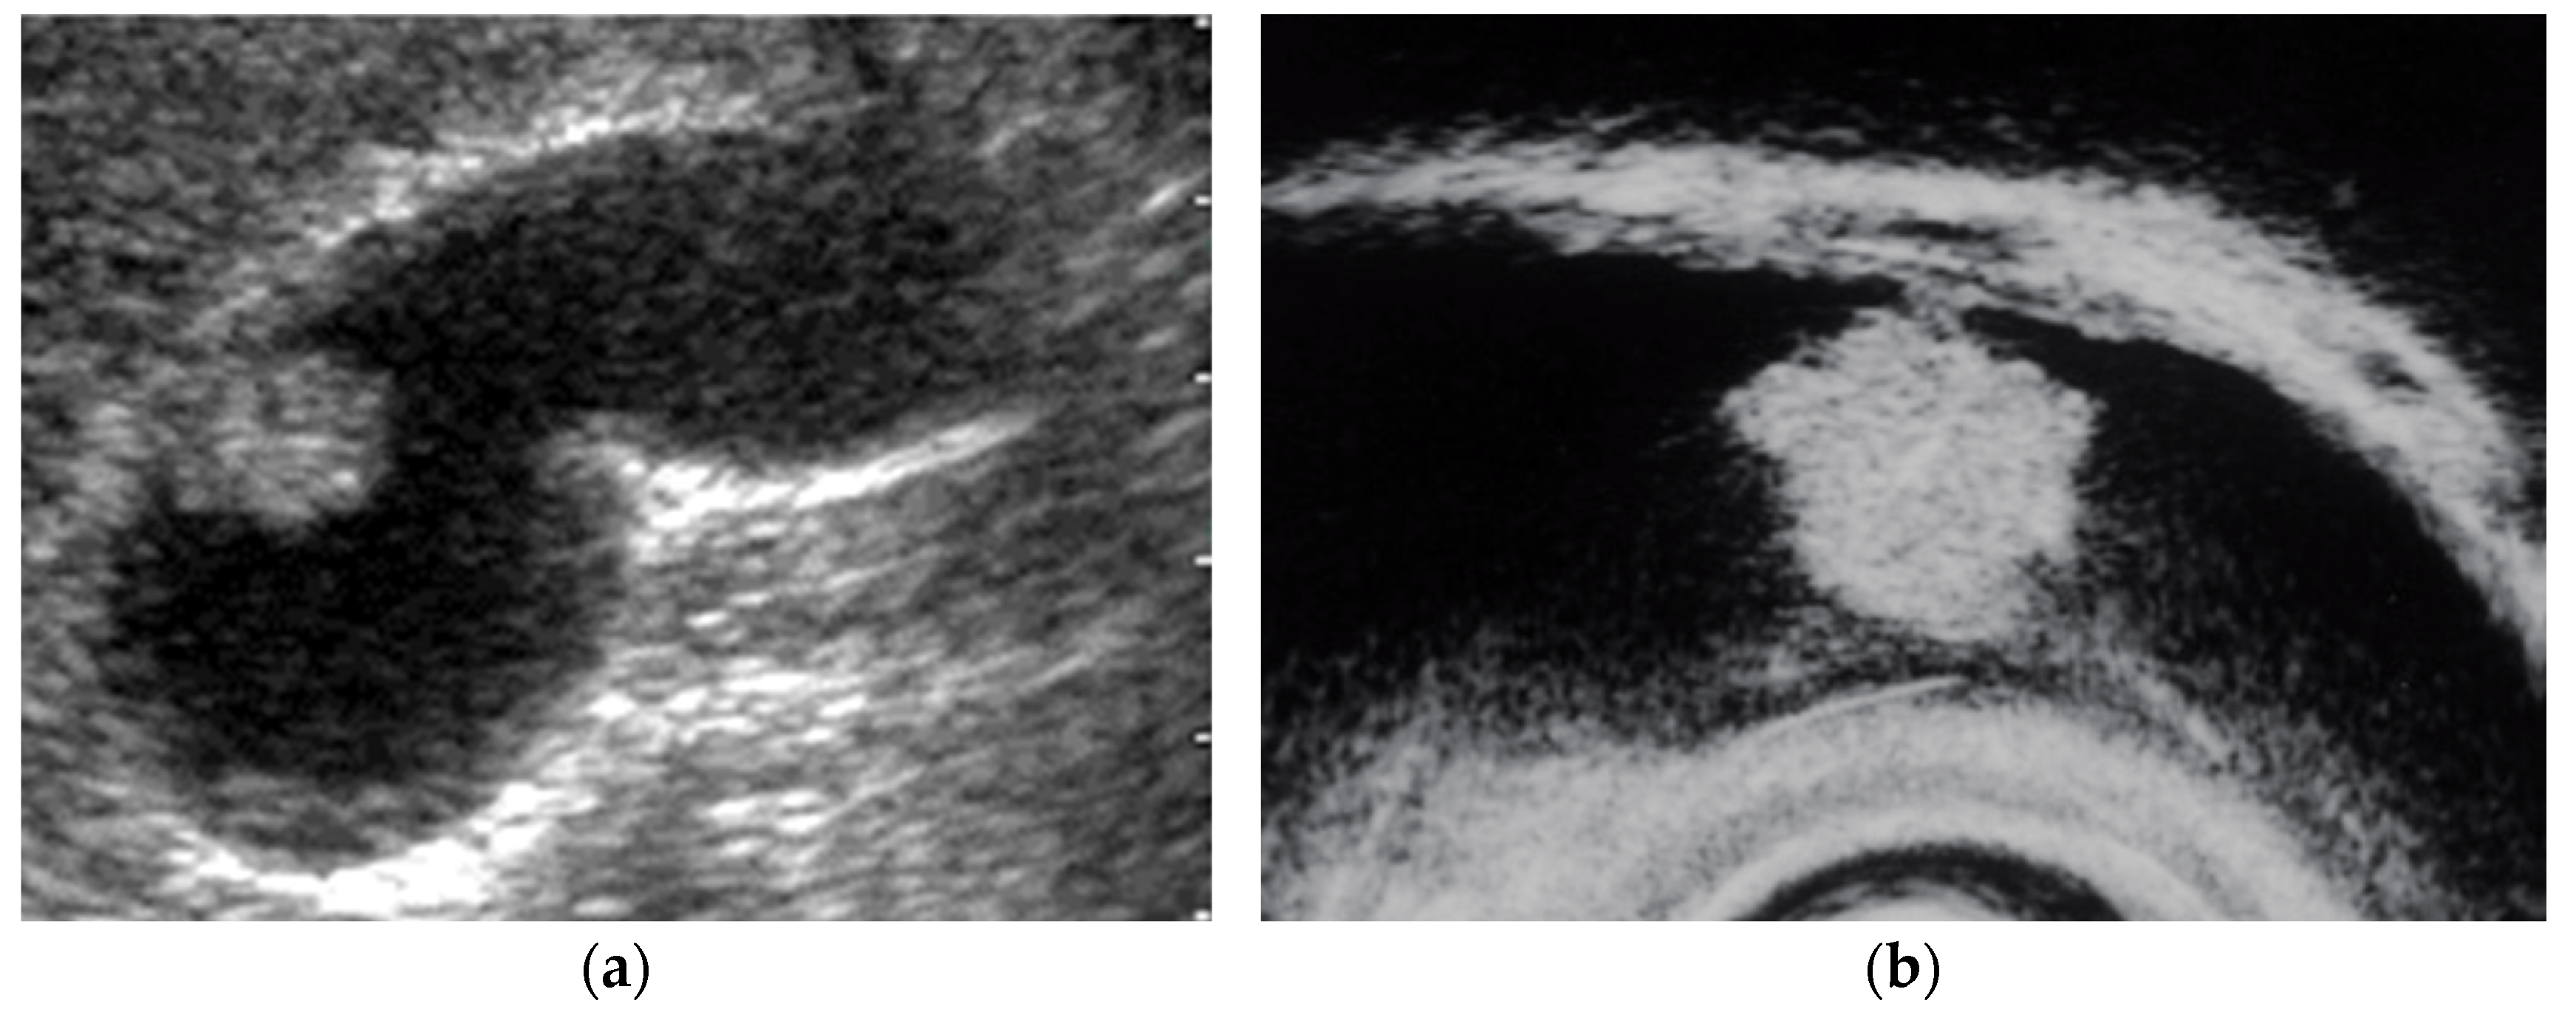

Several studies have evaluated EUS in the differential diagnosis of GB protuberant lesions [22,23,24,25,26,27,28,29]. The differential diagnosis for neoplastic and non-neoplastic lesions is based on size, number, morphology, surface contour, internal echotexture, and internal structure (Table 3). Among these findings, classifying them into pedunculated or sessile (broad-based) types is very important. Most pedunculated lesions are benign, and cholesterol polyps are the most common. Multiple polyps measuring ≤10 mm are highly likely to be cholesterol polyps [30]. However, malignant tumors are included in rare cases. These lesions are frequently incidental findings during abdominal examinations, and precisely distinguishing benign lesions from malignancies is important. EUS can visualize the layered structure of the GB and provide high-resolution images using high ultrasound frequencies. The characteristic findings of cholesterol polyps on EUS are a deeply notched granular surface and morular morphology. The internal echo is rough or granular, and highly echogenic punctiform foci reflecting cholesterolosis are visible (Figure 1) [25]. Peduncles are thin. Thus, they are often unobserved even on EUS [26]. Akatsu et al. [27] described the presence of hyperechoic spots, and multiple microcysts were important indicators of non-neoplastic lesions. Kimura et al. [24] described a granular contour, and a spotty internal echo pattern in the pedunculated polypoid lesions indicated benign pathology.

Figure 1.

Cholesterol polyp. (a) EUS shows a cholesterol polyp as a granular-surfaced pedunculated lesion. The internal echo is heterogeneous with a hyperechoic spot (arrow). (b) Photograph of the gross pathologic specimen after cholecystectomy shows a yellowish polyp. (c) H-E stain of the specimen demonstrates an aggregation of foamy cells under the epithelium.